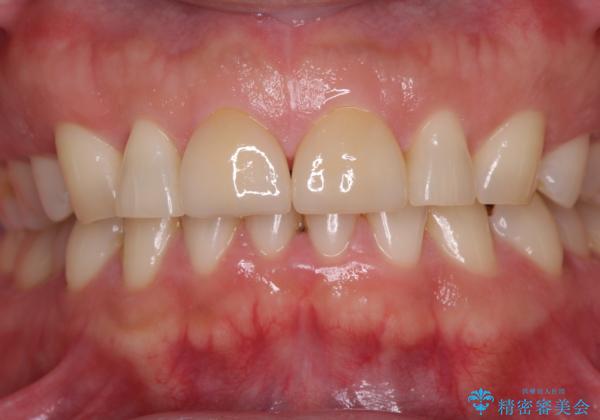

ラミネートベニアは切削量が少ないことがメリットとしてあげられますが、色調を周辺と合わせられないこと、接着境界線が長く汚れや歯石が溜まりやすいことがデメリットとして考えられます。

また、接着境界線にむし歯がある場合には適用外となるなど、適用症例を選ぶため、治療に際して担当医としっかりと相談することが大切です。